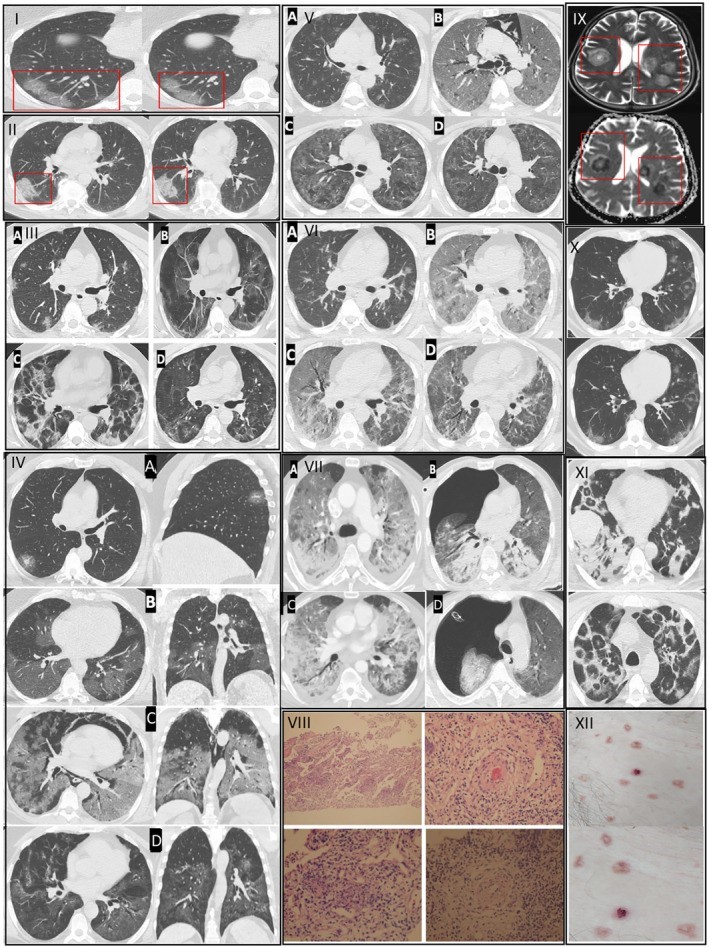

Prof. Dr. Özkaya, Kovid-19’un özellikle kılcal damar düzeyinde ciddi hasar bıraktığını belirterek, "Pandemi boyunca takip ettiğimiz binlerce hastada ‘endotelit’ dediğimiz damar iç yüzeyi hasarının ani ölümleri tetiklediğini saptadık ve uluslararası dergilerde yayınladık. Avrupa Kalp Dergisi’nin son verilerinde de bu durum ‘Kovid-19 sonrası damar yaşlanmasının hızlanması’ olarak tanımlanmıştır. Virüsü geçirenlerde damar yaşı, takvim yaşından daha yaşlı hale geliyor. Bu etki bazı kişilerde 5 yıllık yaşlanmaya eşdeğer" dedi.